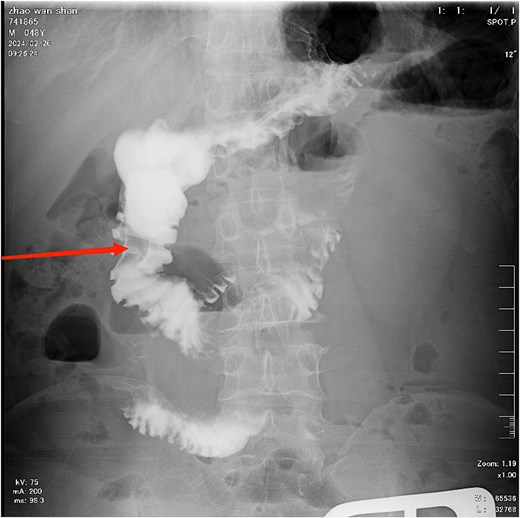

Diagnosis on admission: (i) Acute intestinal obstruction; (ii) Electrolyte disorders (low sodium, low chloride, and low calcium); (iii) Diabetes mellitus; (iv) Gallbladder stones. After admission, water and fasting were immediately given, gastrointestinal decompression, enema, and maintenance of water and electrolyte balance. Further improvement of gastroscopy and colonoscopy showed no obvious abnormalities, and the patient's symptoms improved after conservative treatment. A total of 8 days after admission, the patient experienced worsening epigastric distension and pain. A gastrointestinal contrast study revealed an obstructive lesion located at the terminal ileum (Fig. 2). On the 9th day after admission, an exploratory laparotomy was performed. During the operation, a mixed-type stone measuring ⁓5×5 cm was found ⁓20 cm from the ileocecal valve. A small intestine incision was made to remove the stone, and the specimen was sent to the pathology laboratory for component analysis. Postoperatively, gastrointestinal decompression was continued, and the patient was kept nil by mouth for 6–8 days. The patient was advised to consume a small amount of warm saline, which was tolerated well without discomfort. Subsequently, the patient was allowed to consume a small amount of liquid diet, which was also tolerated without issues. Gastrointestinal decompression and fasting were then discontinued. On the 10th postoperative day, the patient had a bowel movement, indicating that the obstruction had been resolved, and no stenosis was observed at the ileal anastomosis site. The pathology laboratory reported that the submitted specimen consisted of a mixture of cellulose, hemicellulose, and tannic acid. Inquiry of medical history: the patient had previously had discomfort such as upper abdominal distension and pain, occasional nausea and loss of appetite, etc., which were not paid attention to and treated. According to the postoperative pathological component detection combined with clinical manifestations and the patient 's medical history, it can be considered that the terminal ileum stones are derived from gastric stones (Figs 3 and 4).

The contrast study reveals a complete obstruction at the terminal ileum, as indicated by the arrow.